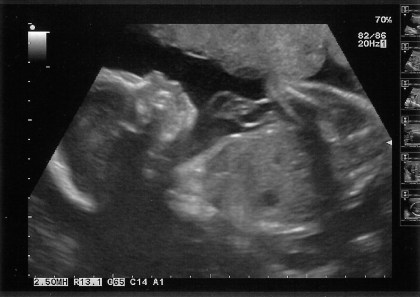

Yesterday I went for my 24 week scan – because the particular clinic I attend is on a Thursday and my weeks change on a Friday I was only 23 weeks 6 days meaning that they couldn’t plot sizes on the graph which annoyingly starts at 24 weeks!

The scan itself was very quick, she quickly found him, took some photos then proceeded to measure his head circumference, abdomen circumference and femur length, she told me my placenta is high anterior and that the fluid levels are normal. I asked how he was laying and she told me that his head was in my pelvis, but not to worry he had plenty of room to move around.

After the scan I was sent to wait to see the consultant and this took a good hour! Basically she just told us what the sonographer had already said, that baby was measuring well, and she also told us that she was going to put a note on my file that baby needs to be checked for an overactive thyroid as soon as he is born, as unfortunately it’s possible it will have been passed on and there is nothing I can do to prevent it. Worryingly the note says “NICU” hopefully that’s just routine and not as scary as it sounds!

After this she asked if we had any questions, which we didn’t, and then that she would sort out so I could book my next scan (which I assumed would be in 4 weeks). When I turned up at reception she booked me in for two weeks, which we only realised when I noticed my name was already in the book at a different time (for my clinic only endocrinology appointment). I told her that the scan should be in another two weeks after that and she told me the form she had been given said scan in 2 weeks! She went to check and the consultant confirmed that she wanted another scan in 2 weeks. She hadn’t mentioned this to us so I’m assuming there isn’t a particular reason for halving the gap between these scans – I’m not complaining, they can check on him as much as they like, but I’m just hoping they didn’t find something they’re not telling me about. So that should be interesting on May 1st to see what happens!